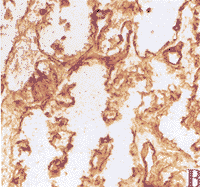

晚期继发青光眼病人视乳头Ⅳ型胶原蛋白免疫过氧化酶染色结果表明,与正常成人视乳头细胞外基质相比[4],发生了明显改变。纵切观察,筛板前区后凸,神经束消失,大部分空间由Ⅳ型胶原蛋白阳性染色物填充。筛板部表现为筛板的塌陷、重叠和融合,胶原蛋白Ⅳ阳性反应密度明显增加,且进入到筛孔中。筛板后区为神经束膜Ⅳ型胶原蛋白染色密度增加(附图)。

附图:继发表光眼视乳头筛板IV型胶原蛋白免疫组化染色

A:纵切观察 12× a:筛板前区 b:筛板 c:筛板后区

B:筛板后区 100×

层连接蛋白染色方式与Ⅳ型胶原蛋白相同。